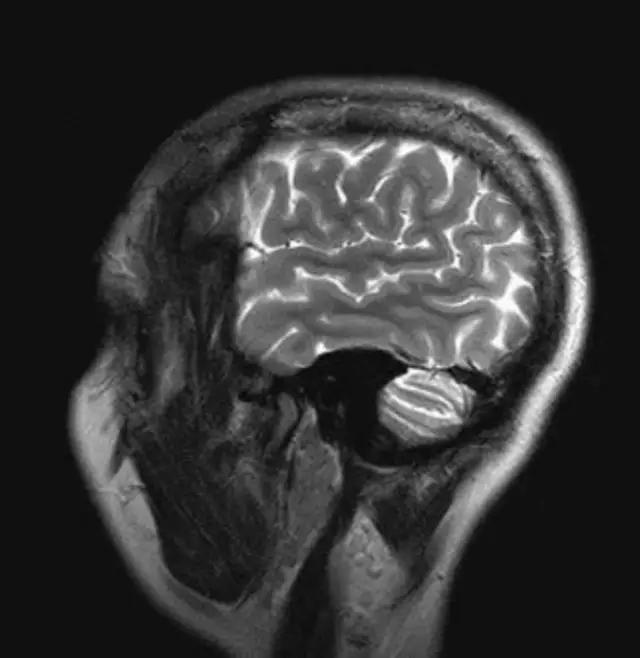

MRI最适宜的检查部位——

1、颅脑

下图是同一个病人的MRI照片,MRI显示的内容更多,包括骨与软组织等,很多早期的、细微的病变都能清晰显示,其诊断报告对病人造成的影响也更大!